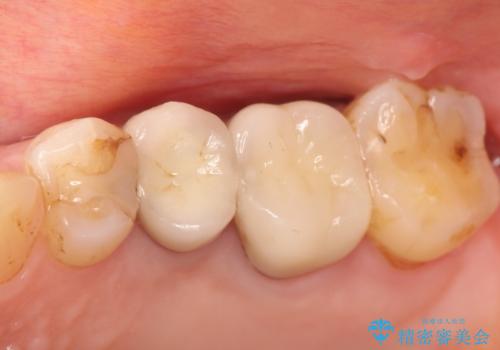

- 以前から奥歯に違和感があることを主訴に来院されました。歯肉にサイナストラクトを認めたため、再根管治療を行った後オールセラミッククラウンにて修復治療を行いました。根管治療は林先生に依頼しております。

- 13万円(根管治療別途)費用は治療当時の料金となります

根管治療後は、破折リスクが高まるため被せものによる治療を提案いたします。